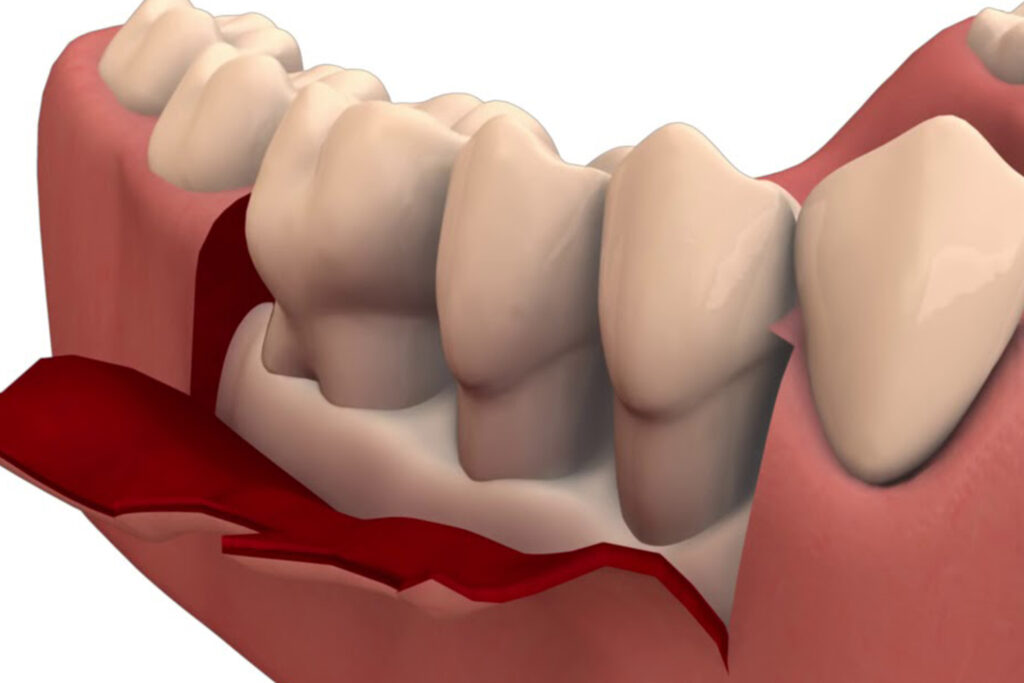

Pocket reduction, also known as periodontal pocket reduction, is a dental procedure used to treat periodontal disease, which is an infection of the gums and surrounding structures that support the teeth. The procedure is used to reduce the depth of periodontal pockets, which are spaces that form between the gums and teeth as a result of gum disease.

Pocket Reduction

The dentist or periodontist will then use special instruments, such as ultrasonic scalers or hand instruments, to remove the infected tissue and smooth the roots of the teeth. This helps to reduce the depth of the periodontal pockets and encourage healthy tissue growth.

Tissue Regeneration

Depending on the case, regenerative procedures like Bone Grafting, Guided Tissue Regeneration or Enamel Matrix Derivative (EMD) may be added to the procedure to further support the healing process.